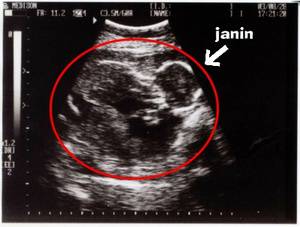

Gambar Usg Kista

MACAM-MACAM KISTA. Dari USG bisa… - dr Yudhistya SpOG | Facebook Ingin Terhindar dari Kista? Jauhi 4 Jenis Makanan Enak Ini Sekarang! - Semua Halaman - Grid Health MACAM-MACAM KISTA. Dari USG bisa… - dr Yudhistya SpOG | Facebook BILIK SONOGRAFER : Kista Ovarium MACAM-MACAM KISTA. Dari USG bisa… - dr Yudhistya SpOG | Facebook MACAM-MACAM KISTA. Dari USG bisa… - dr Yudhistya SpOG | Facebook Ahli Kista: Pastikan Kista Anda dengan USG Bagaimana mendeteksi penyakit kista ovarium? - Quora Kista Berujung Kematian, Segera Operasi ! | Daniel Kista Ovarium. - ppt download Kista 5 Kg Ibu Hamil Hilang Tanpa Operasi Halaman all - Kompasiana.com Kesha Ratuliu Ungkap Hasil USG Payudara, Jangan Tertukar, Ini Beda Tumor dan Kista - TribunStyle.com Benarkah Kista Bisa Disembuhkan dengan Kehamilan? Jangan Salah Kaprah, Ini Penjelasan Medisnya KASUS PILIHAN: KISTA COKLAT. APA ITU?… - dr Yudhistya SpOG | Facebook Dikira Cuma Masuk Angin, Dokter Ini Tercengang Saat Temukan Kista Sebesar Bola Sepak di Dalam Perut Pasiennya! - Semua Halaman - Grid.ID Punya Kista Endometriosis dan Rahim Retro, Eh HAMIL – Dessy Donat Ada kista bisa hamil juga kok… | Dr Suryo, SpOG - Kesehatan Reproduksi Kesha Ratuliu Ungkap Hasil USG Payudara, Jangan Tertukar, Ini Beda Tumor dan Kista - TribunStyle.com Kista di Rahim | Sehat PLUS Cantik Menjawab Masalah Kista Indung Telur: Bisa Hamil Apa Nggak?? Harus Operasi Apa Nggak?? (*&*^$%#%$# | Dr Suryo, SpOG - Kesehatan Reproduksi Mioma, Kista & Ambeien | Sehat PLUS Cantik Bom Waktu bernama Kista Ovarium!!! – ask-dr. David Mayndra Utama, SpOG Kisah Shireen Sungkar Punya Kista 11 Cm - Tabloidbintang.com Agar Kista Tidak Berkembang Menjadi Besar | Republika Online USG Transvaginal - Blog Positif Endometrosis - Catatannike.com Testimoni | Dr Suryo, SpOG - Kesehatan Reproduksi Kista di luar rahim.. help me bund.. - IbuHamil.com Cara Menghilangkan Penyakit Kista Ovarium Punya Kista Endometriosis dan Rahim Retro, Eh HAMIL – Dessy Donat Kenali Gejala Kista Ovarium Dikira Cuma Masuk Angin, Dokter Ini Tercengang Saat Temukan Kista Sebesar Bola Sepak di Dalam Perut Pasiennya! - Semua Halaman - Grid.ID La Rosiantes et Lahardos: Kista??? Oh Noooo… USG Ascites & Kista Ovarium Pemeriksaan abdomen pada kista ovarium - YouTube Steemit-Health #1: Kisah Operasi Kista Ovarium pada Bocah 10 Tahun (Indonesian Version) — Steemit Cara Membaca Foto USG: 8 Langkah (dengan Gambar) - wikiHow Foto Pertama USG Bukan Foto Janin | M I N E Kapan Kista Ovarium Dianggap Bahaya dan Harus Dioperasi? Kista ovarium KISTA INDUNG TELUR | 4healthylifetransferfactor 5 Fakta Kista Coklat yang Harus Diketahui | Popmama.com Kerap Makan Makanan Instan dan Pedas Tapi Jarang Makan Nasi, Perempuan Ini Alami Hal Menakutkan Sampai Harus Operasi - Semua Halaman - Nakita Miu Twitter: “Tadi abis di USG ternyata aku punya kista:") untung belum besar bgt tp tetep aja takut hehe… " 6 Tanda Anda Mengidap Kista Ovarium Retha Silaen ar Twitter: “@dr_Bambang_SpOG Dok, mau tny apakah rahim saya normal? Waktu usg transv ketika haid ada kista 2cm ktanya. Thx http://t.co/6BX9YyPMK7” Kenali Perbedaan Miom dan Kista - Investor.ID Ovarium, Ultrasonografi Ginekologi, Folikel Ovarium gambar png Penyakit Kista Indung Telur Rentan Menyerang Wanita | Xylem Penyebab Kista pada Wanita, Gejalanya hingga Cara Menghindarinya - Semua Halaman - Grid Health Jangan Takut dengan Kista Ovarium - Alodokter hasil-USG-kista-ibu eno | Nila Sari | Flickr Takut Tak Bisa Hamil Karena Kista, Shireen Sungkar Malah Hamil Anak Kedua - Banjarmasin Post Kista Bukan Kanker!! LAPORAN KASUS Kesha Ratuliu Ungkap Ukuran Tumor Payudaranya : Okezone Celebrity Assalamualaikum Bun , tadi saya baru usg soalnya bbrp Kista Dermoid Penatalaksanaan pasien pasca histerektomi Mama Ketahui Fakta Mengenai Kista saat Hamil - Mamapapa.id % Terjadi Lagi, Bayi Baru Lahir Ini ‘Mengandung’ Janin Kembarannya Sendiri Sejak dalam Kandungan - Semua Halaman - Grid Health 7 Gejala Kista Ovarium Kanan di Awal, Wanita Wajib Tahu! | Diadona.id Kista Fungsional, Bahaya Nggak Sih ? – esshintaku Tri Lestari Handayani, SKp.,M.Kep.,Sp.Mat - ppt download Penatalaksanaan pasien pasca histerektomi Ocha’s Pregnancy Diary: September 2017 Kenali Kista Ovarium Sebelum Terlambat | Dokter.my USG Ascites & Kista Ovarium Unggah Hasil USG Kesha Ratuliu Dibully, Dituding Hamil di Luar Nikah, Padahal Itu Tumor di Payudara - Pojoksatu.id Aku dan Kista Tiroid - Novarty Hamil kosong Tanpa Kuret, Ternyata Ini Dampaknya Moms! Kista endometriosis bikin down.. - IbuHamil.com Ratih Wiji Ningrum: Kista Endometriosis dan Visanne Dienogest Tumor Kandungan Mioma Kista | pengobatan penyakit tumor | gangguan kesuburan Program Hamil (Promil) | FuschiaGrey Pengalaman Menghadapi Kista Ovarium Tanpa Operasi - Ella Fitria Cara Membaca Foto USG: 8 Langkah (dengan Gambar) - wikiHow Kista Ovarium.ppt 5 Langkah Membaca Hasil USG yang Bisa Bunda Pelajari Diagnosis Mola Hidatidosa - Alomedika Kista ovarium Berhasil hamil dengan kista coklat | Dr Suryo, SpOG - Kesehatan Reproduksi Obat Herbal untuk Kista dan Miom Paling AMPUH dan AMAN - Posts | Facebook Penyebab Kista Ovarium dan Gejalanya - Mamapapa.id % Kista? Glucogen Solusinya - Irma Vania Oesmani MELAWAN KISTA RAHIM / KISTA OVARIUM : apa itu? dan bagaimana saya mengatasinya? | Yubikanobi DUA MINGGU SAJA KISTA HILANG, SAYA HAMIL | Breakthrough Generation Nyeri Perut karena Kista 10cm Mengecil dengan Varash Classic – Varashoil USG Transrektal Adalah Sejenis USG Panggul, Apa Fungsinya? kista | Dr Suryo, SpOG - Kesehatan Reproduksi Kenali Perbedaan Tes USG Abdominal dan Transvaginal Semua Akan Terjawab di Waktu yang Tepat - kumparan.com Ocha’s Pregnancy Diary: HASIL USG PERTAMA lapkas kista ginjal Cara Membaca Foto USG: 8 Langkah (dengan Gambar) - wikiHow Penyakit Kista Dentigerous - Gejala, Penyebab, Pengobatan - Klikdokter.com Biaya USG untuk penyakit dalam - YouTube Unggah Foto USG, Kesha Ratuliu Dikira Hamil Padahal Belum Nikah. Ternyata itu Bukan Foto Rahim April | 2015 | Dr Suryo, SpOG - Kesehatan Reproduksi | Page 2 Penatalaksanaan pasien pasca histerektomi